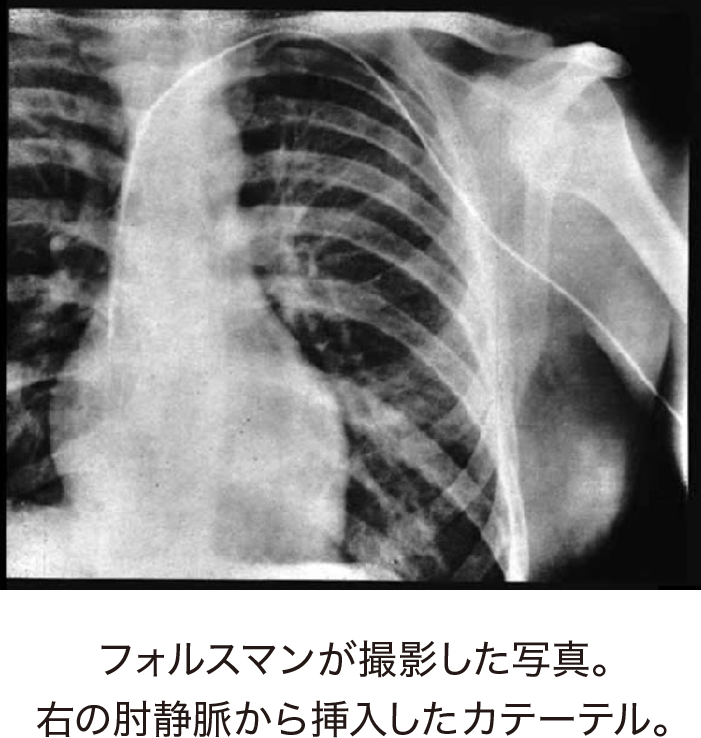

動物と同様にヒトの心臓にもカテーテルを入れられれば、素早く確実に薬剤を投与できるのではないか。そう考えたのがドイツの医師ヴェルナー・フォルスマンです。1929年、25歳の新米医師フォルスマンは自らの肘の内側を切開し、静脈にカテーテルを挿入したのです。彼の肘静脈には尿管カテーテルが30センチほど挿入され、X線室に移動。胸部をX線透視装置で確認しながらカテーテルを動かしたのです。カテーテルは脇と鎖骨の下を通り、ついに心臓の右心房まで到達します。半ば強引な方法でしたが、心臓カテーテル実験は成功を収めました。ちなみに彼はこのとき、実験の証拠を残すためにX線写真を撮影しています。(写真)